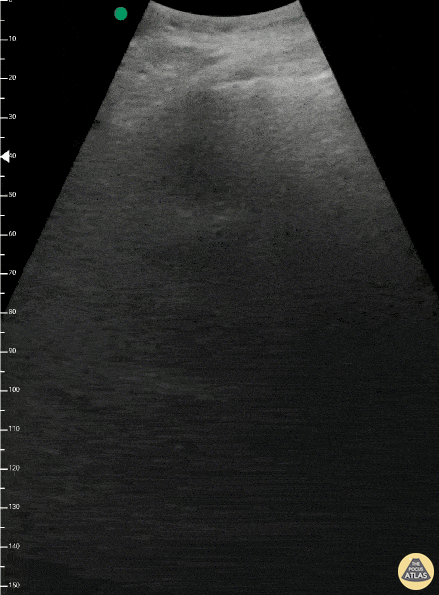

Pulmonary - Light Beam Sign (COVID-19)

Seen here is a "Light Beam Sign" in a patient with COVID-19 pneumonia. The on-and-off effect of the hyperecchyoic vertical artifact is believed to occur as a result of ground glass alterations in lung parenchyma. At times the light beams or B-lines cover A-lines; and at other times the A-lines remain visible in the background. Renato Melo, Emergency Physician at Hospital das Clínicas de Marília-SP, Brazil. Co-founder of Pocus Jedi @Renato_Melo_